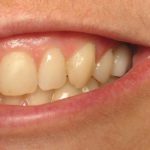

Erin

This patient had a implant place to replace a tooth which had been removed due to infection.